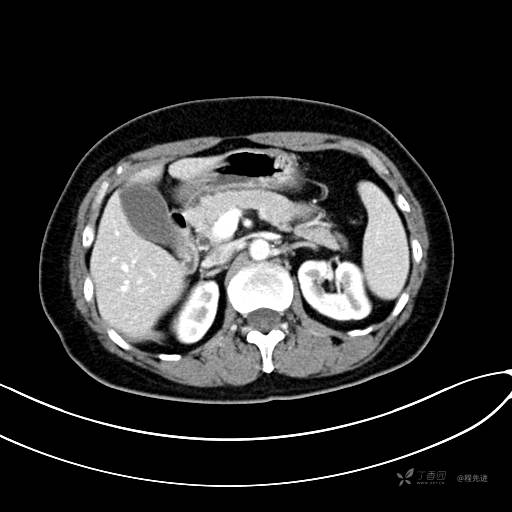

CT增强动脉期